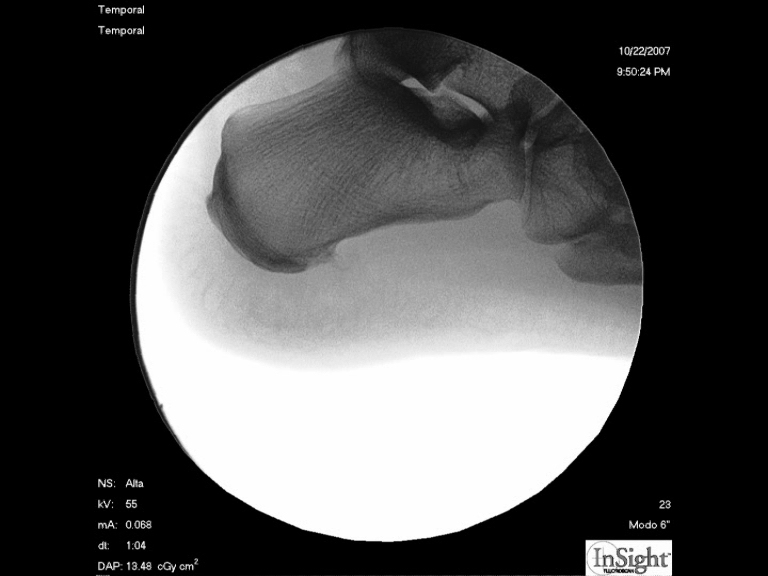

Foto 8

En un control final con rayos-x podemos ver como se ha limado la prominencia |